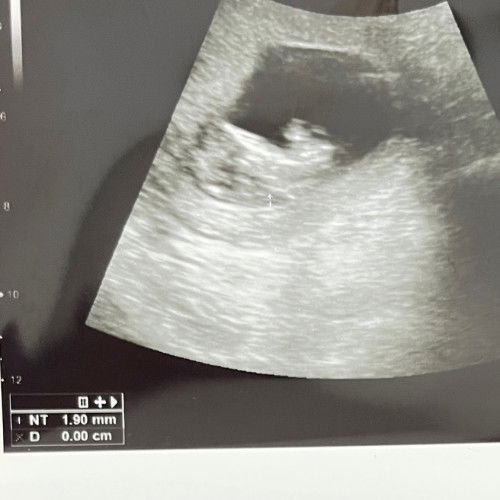

ukuran NT umur kehamilan 11w3d

Sharing dong bun, usia kehamilanku 11w3d dan aku screening NT 1.90mm apakah itu normal. Yg udah screening MT boleh dong share hasilnya. Kata dokterku bagus2 aja tapi ttp worry. #pregnancy #Sharingdong_Bund